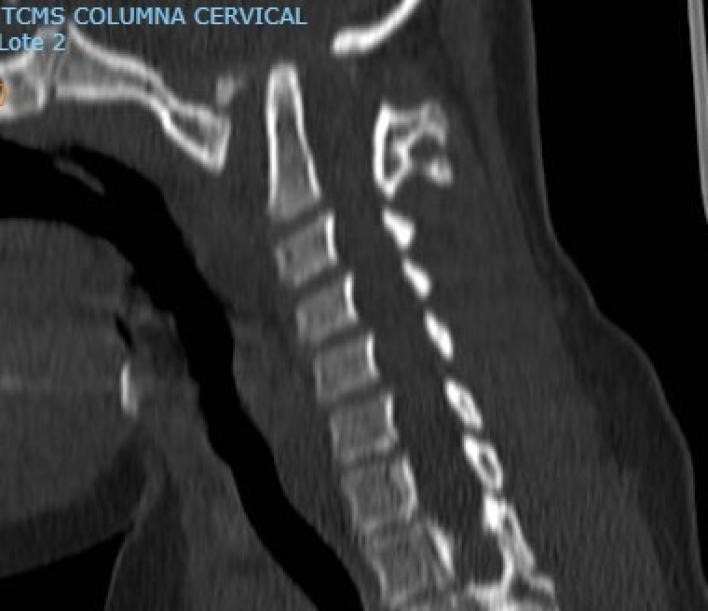

Se decide internación por síndrome medular agudo, y se realizan estudios por imágenes donde se observa lesión medular con mielomalacia debido a mal formación en charnela con inestabilidad atlanto axoidea y estrechamiento del foramen (Figuras 1, 2 y 3). En tomografía se observa agenesia del arco posterior del atlas con displasia de macizos laterales (Figura 4).

Figura 4: Tomografía sagital preoperatoria